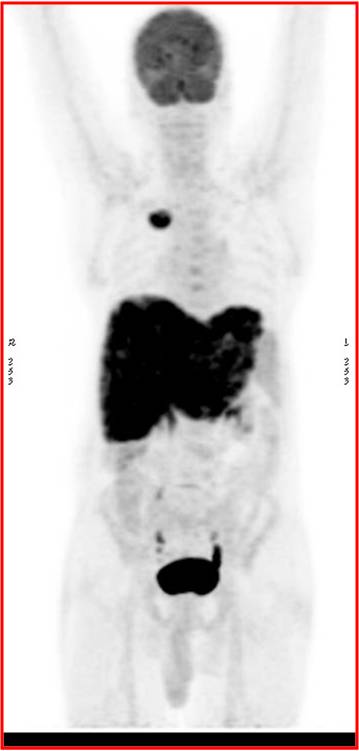

CT scan of the abdomen confirmed the findings ; For further clarification PET whole body scan was done at a centre in Chennai. The following images are from that.